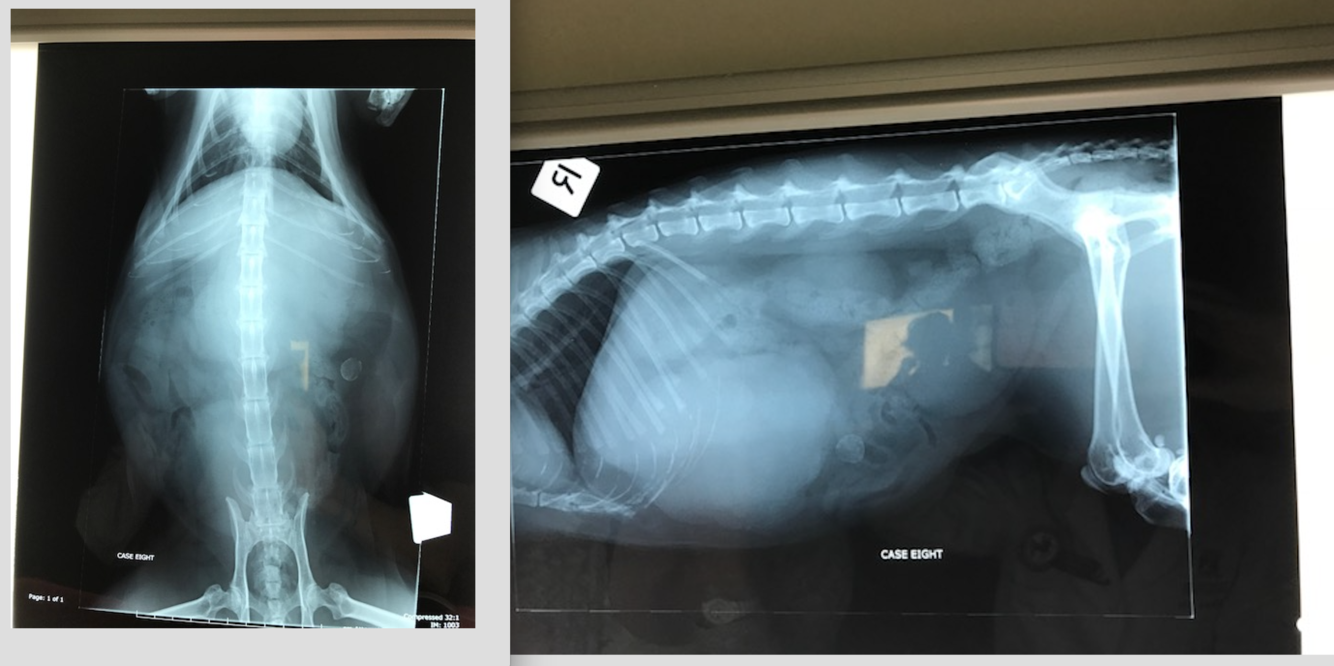

11 yo FS Maltese Terrier

Not quite right for a couple days now, vomiting

HR RR WNL- pendulous abdomen, not painful on palpation. V+ and diarrhoea

DDX intraabdominal decreased serosal detail? Most likely?

Hepatomegaly- what are the rules for assessing liver ? DDX?

Gas distended SI…

Fragmented mineral opacity in the descending colon….